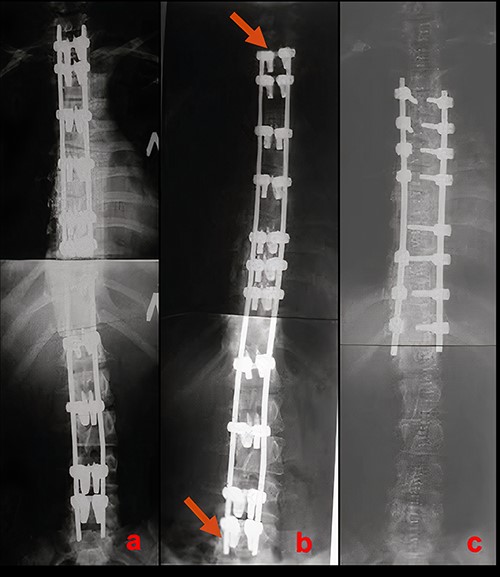

Radiographic results of surgical treatment. (a) AP X-rays of the patient’s spine in standing position after the 1st stage of surgical treatment on the 5th day after surgery. Residual deformity of the spine was 15°. (b) AP X-ray of the patient’s spine in a standing position 4 years after surgery. Growth of the spine and the associated shortening of the free upper and lower ends of the plates can be observed (red arrows). (c) AP X-ray of the patient’s spine after the 2nd stage of surgical treatment. The angle of residual deformity is < 5°.

At a 4-year follow-up at the age of 16, the spine grew by 5 cm. The patient’s sitting height was 80 cm. Shortening of the free ends of the plates at the upper and lower ends of instrumentation, associated with the continued growth of the spine could be clearly visualized (Fig. 3b).

As the second stage of surgical treatment, the LSZ system was removed and definitive T4-T12 instrumentation was performed. The duration of the surgery was 203 min. Blood loss amounted to 450 ml. Postoperative radiographs demonstrated 94% deformity correction (compared with deformity before index surgery) (Fig. 3c). The patient was mobilized on Day 2.